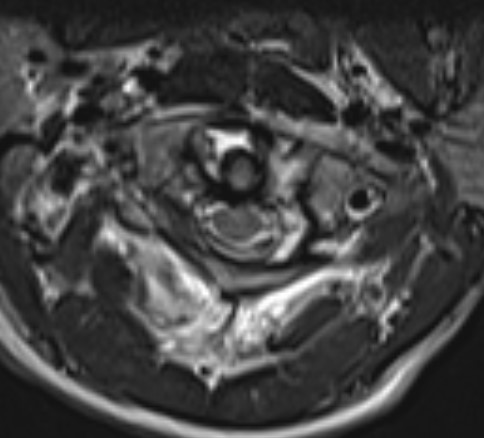

MRI

Assess ligamentous injury, specifically transverse ligament

MRI demonstrating intra-ligamentous injury (blue arrow)

Jefferson MRI 1Jefferson MRI 2

MRI demonstrating avulsion of the TAL on the left side